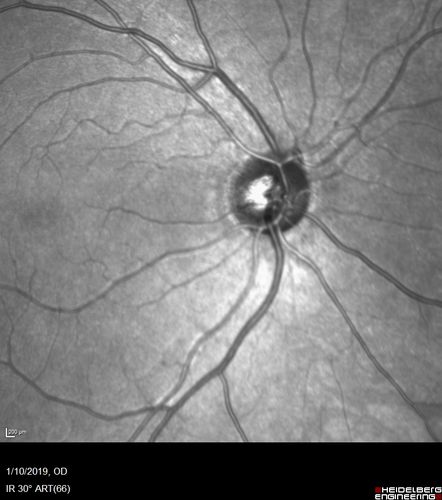

Melanocytoma - Lightly Pigmented

42 year old female with very mild visual field and vision loss in the left eye: 20/20 OU